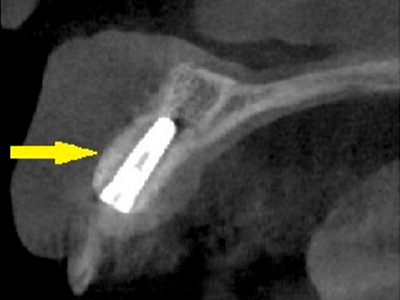

移植した骨が周囲の骨と結合したのを待ち、6か月後にインプラント埋入手術を行いました。

写真がインプラント埋入後のCT画像で、黄色矢印に示すようにインプラントが2本埋入できました。 -

インプラント埋入後の、別な方向からみたCT画像です。

神経の通る管にややギリギリでしたが、神経は傷つけずにインプラントが埋入できました(黄色矢印)。